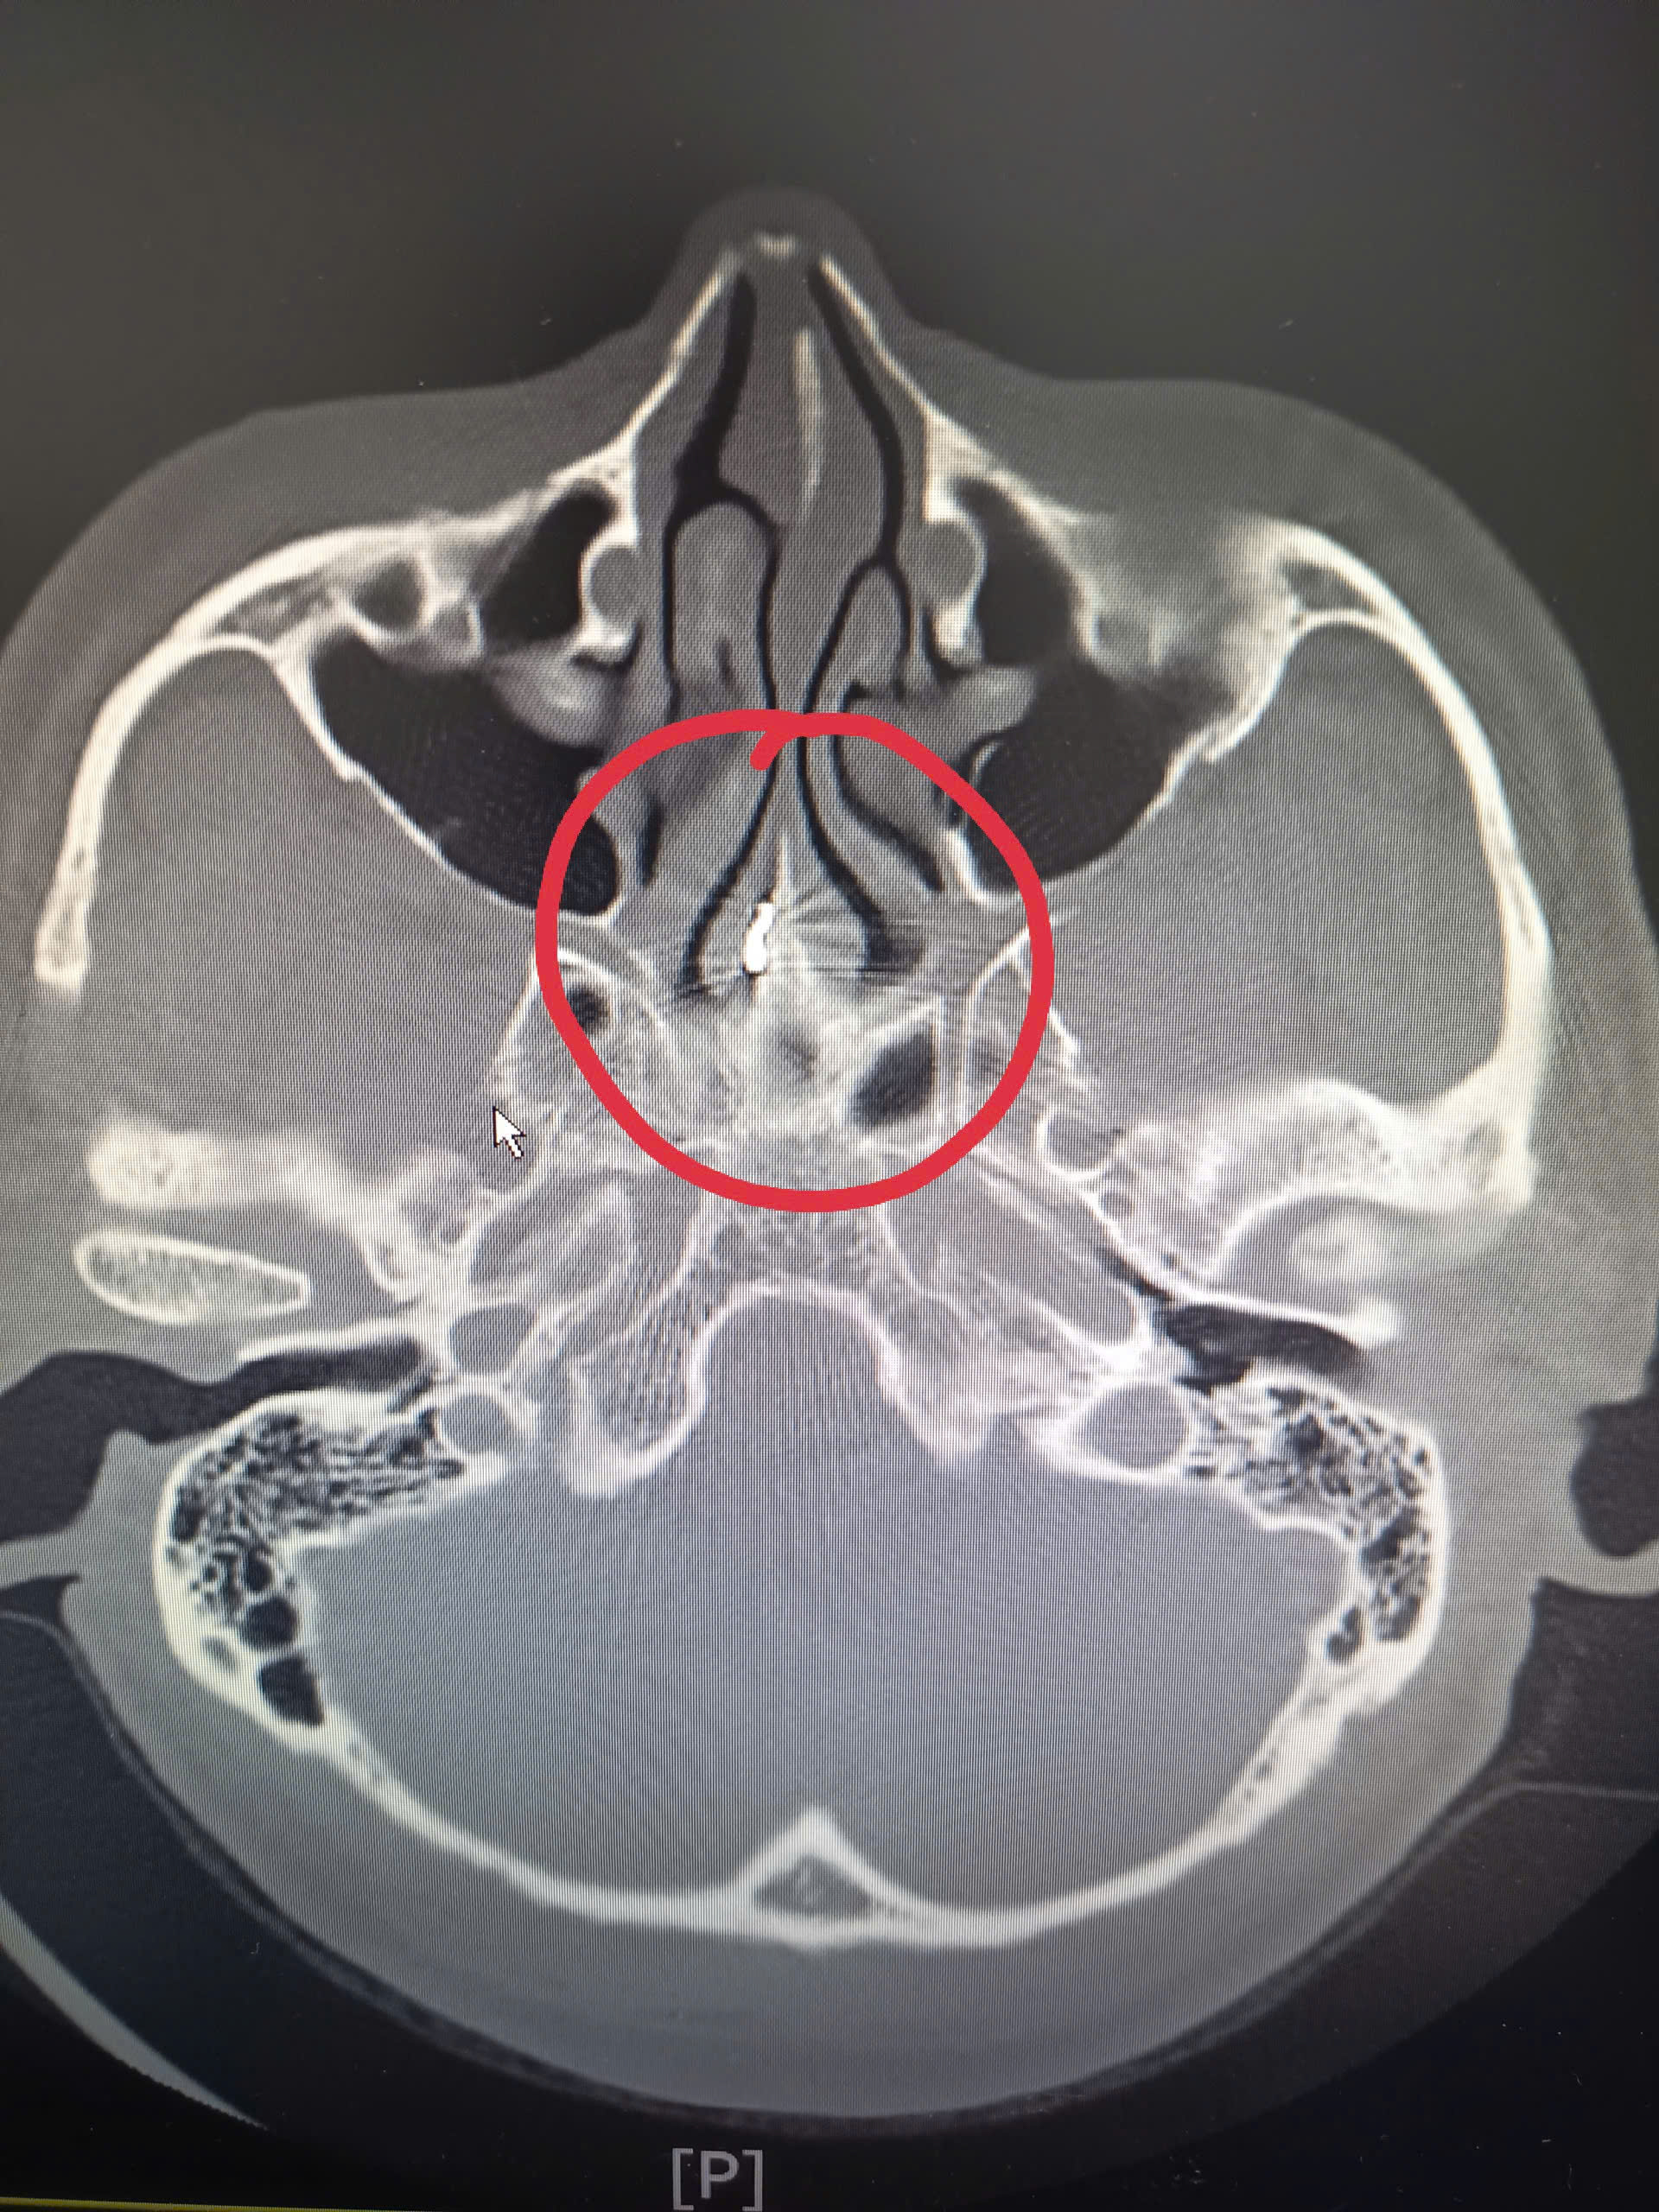

Tại lần thăm khám này, bệnh nhân được chỉ định nội soi Tai Mũi Họng kết hợp chụp cắt lớp vi tính (CLVT) xoang. Kết quả nội soi cho thấy vách ngăn mũi bị thủng, niêm mạc có những biến đổi viêm mạn tính. Đặc biệt, hình ảnh CLVT phát hiện dị vật cản quang nằm ở phần sau – trên của vách ngăn mũi phải, cách cửa mũi trước khoảng 7 cm, sát mặt trước xoang bướm.

Theo các bác sĩ, kết quả CLVT có ý nghĩa quyết định trong việc xác định chính xác vị trí dị vật, qua đó làm rõ nguyên nhân gây viêm mạn tính kéo dài và triệu chứng đau đầu dai dẳng suốt nhiều năm của người bệnh.

Trong quá trình phẫu thuật, các bác sĩ đã lấy ra thành công dị vật tồn dư, nhiều khả năng là mảnh dụng cụ phẫu thuật bị gãy từ ca mổ năm 1984. Dị vật nằm sâu, sát vùng trước xoang bướm – vị trí khó tiếp cận, lý giải vì sao các lần phẫu thuật trước đó không phát hiện được.